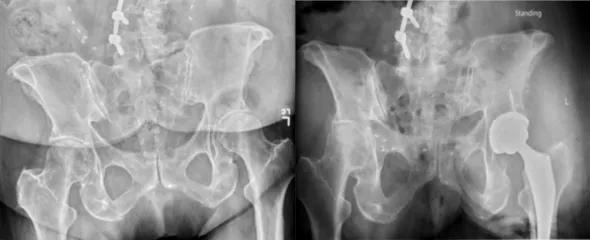

For example, patients with significant lumbar lordosis will have anterior pelvic tilt, as illustrated in Figure 1. In contrast, patients with loss of lordosis, which can occur in cases of ankylosing spondylitis or following repeated spine surgeries, will present with posterior pelvic tilt, as shown in Figure 2. It has been calculated that every 1° of pelvic tilt leads to a functional correction of radiographic acetabular anteversion and inclination of roughly 0.7°. Therefore, the sole use of anatomic landmarks can lead to acetabular component malpositioning.

Figure 1. Radiographs showing characteristic anterior pelvic tilt in a patient with significant lumbar lordosis.

Figure 2. Radiographs showing characteristic posterior pelvic tilt in a patient with loss of lordosis.